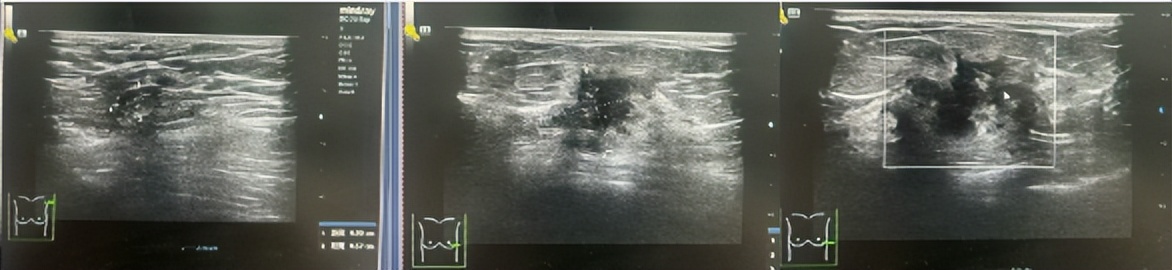

·乳腺DR

图3.2023年6月27日乳腺DR结果

1、左乳外下象限前中带肿块,恶性可能。(BI-RADS 4C)

2、右乳外上象限中后带局限性非对称致密,建议进一步检查。(BI-RADS 0)